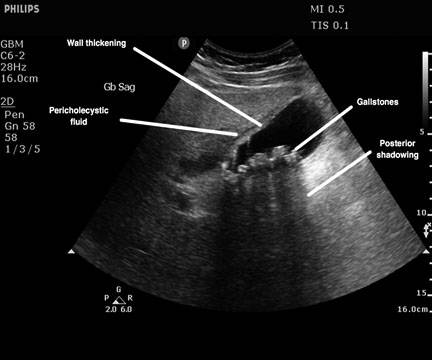

我国胆囊结石主要的发病危险因素包括油腻饮食、肥胖、脂肪肝、糖尿病、高血压、高脂血症、缺乏运动、不吃早餐和胆囊结石家族史等。 可能的保护因素包括增加运动、高纤维饮食、多吃水果、多吃坚果、素食和饮咖啡等,但目前仍存有争议。腹部 B 超是发现胆囊炎和胆囊结石最常用也最有价值的方法,诊断准确率达 95%以上,灵敏度和特异度都很高。因此体检时可通过腹部 B 超(一般肝胆胰脾一起看)进行筛查。

来源:Gallstones and Associated Complications. Emergency Medicine Reports, June 15, 2016.

上图为胆囊结石、慢性胆囊炎急性发作的超声图像。图中黑色的部分是胆囊腔体,一颗一颗的圆形隆起就是的石头,图中还可以见到胆囊壁增厚以及周围有渗出。

体检如果发现了有胆囊炎和胆囊结石,建议挂个普外科看看,由外科医生判断是否有治疗的必要,治疗包括药物治疗和手术治。如果不关注不处理,有可能单纯的胆囊炎也会慢慢向其他并发症演变,包括急性发作后引起胆囊穿孔、胆源性胰腺炎、胆石性肠梗阻甚至胆囊癌。